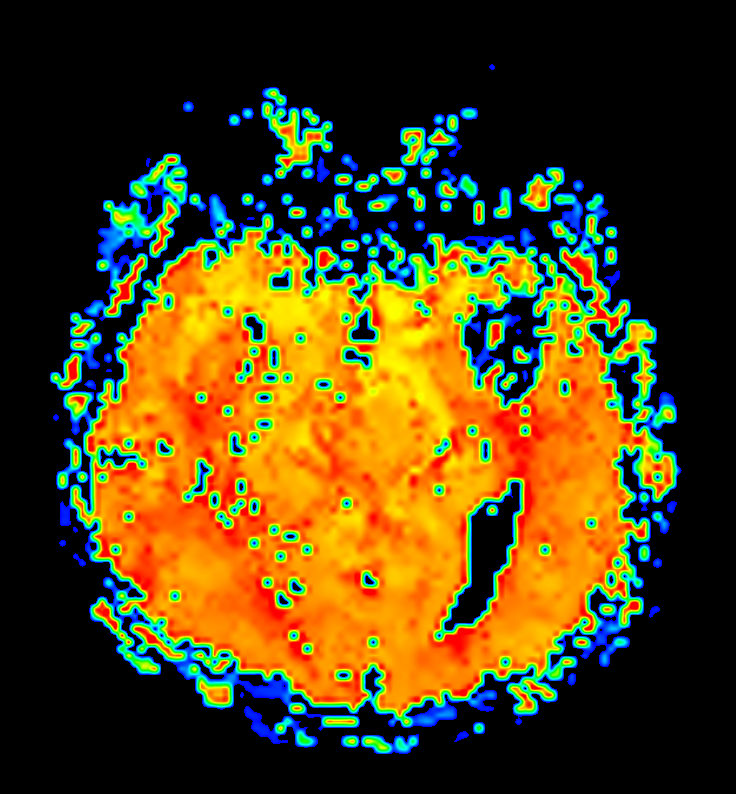

Axial T2* Perfusion (TTP)

-